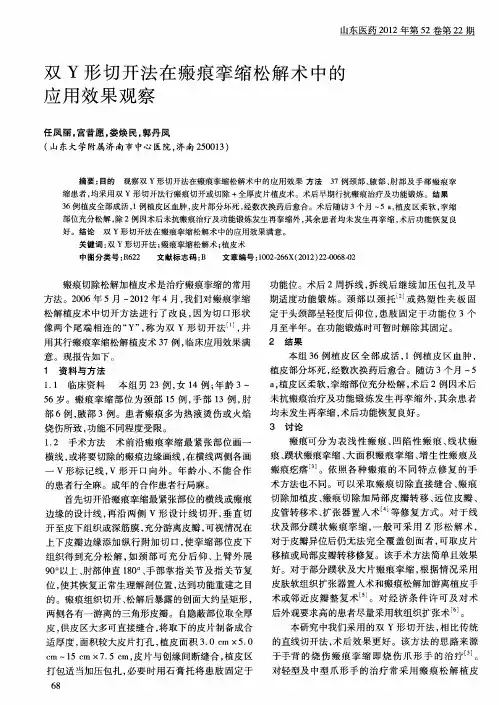

短篇论著烧伤后瘢痕癌七例的临床分析梁伟强张金明潘淑娟陈宇宏宾莲洁冀晨阳韦喆摘要目的探讨烧伤后瘢痕癌的临床特点与手术治疗方法。

方法2001年7月至2010年6月收治7例患者8处烧伤后瘢痕癌病灶,予7处病灶行手术扩大切除肿物,同时松解瘢痕挛缩,并采用整张中厚皮片、全厚皮片移植或皮瓣移植修复创面,另1处病灶行截肢术。

结果5例肿物位于下肢,全部病理诊断均为高分化鳞癌。

术后全部植皮或皮瓣均成活,伤口愈合良好,瘢痕挛缩基本矫正。

所有患者随诊3个月至3年,1例上肢截肢患者术后2个月发现腋窝淋巴结转移,1例患者于术后3个月局部复发。

结论下肢为烧伤后瘢痕癌的好发部位,高分化鳞状细胞癌为烧伤后瘢痕癌最常见的病理类型。

烧伤后瘢痕癌术前要行病理活检明确诊断,切除范围要充分并行植皮等方法修复或行截肢术以避免肿瘤复发。

关键词肿瘤,鳞状细胞;烧伤;瘢痕烧伤后瘢痕癌指烧伤后的瘢痕组织因慢性破溃所致的恶性变,亦名M ar j oli n 溃疡,临床相对少见。

中山大学孙逸仙纪念医院整形外科对2001年7月至2010年5月收治7例烧伤后瘢痕癌患者病灶行手术扩大切除并予植皮或皮瓣移植修复,或截肢术,效果尚满意,报道如下。

一、资料与方法1一般资料:本组7例患者,男4例,女3例,年龄32~80岁,平均531岁。

从烧伤到肿物出现时间约20~41年,平均337年;从肿物出现到就诊时间约6个月至5年,平均2年。

其中4例病灶位于腘窝和(或)小腿,1例位于足背,1例位于腋窝,1例位于右手背、前臂及左手背;面积大小为(6~10)c m (10~22)cm 。

全部瘤体均见菜花样肿物,质脆易出血,中央可见大小不等溃疡形成,并有恶臭分泌物。

7例患者8处病灶术前病理结果均为高分化鳞状细胞癌。

2方法:7例患者7处病灶行肿物扩大切除,3例行皮瓣转移修复,4例行皮片移植修复;1例患者1处病灶行前臂上段截肢术。

硬外麻或全麻后,在肿瘤边缘约2~3c m 用画线笔或美蓝作切除范围的手术切口标记。